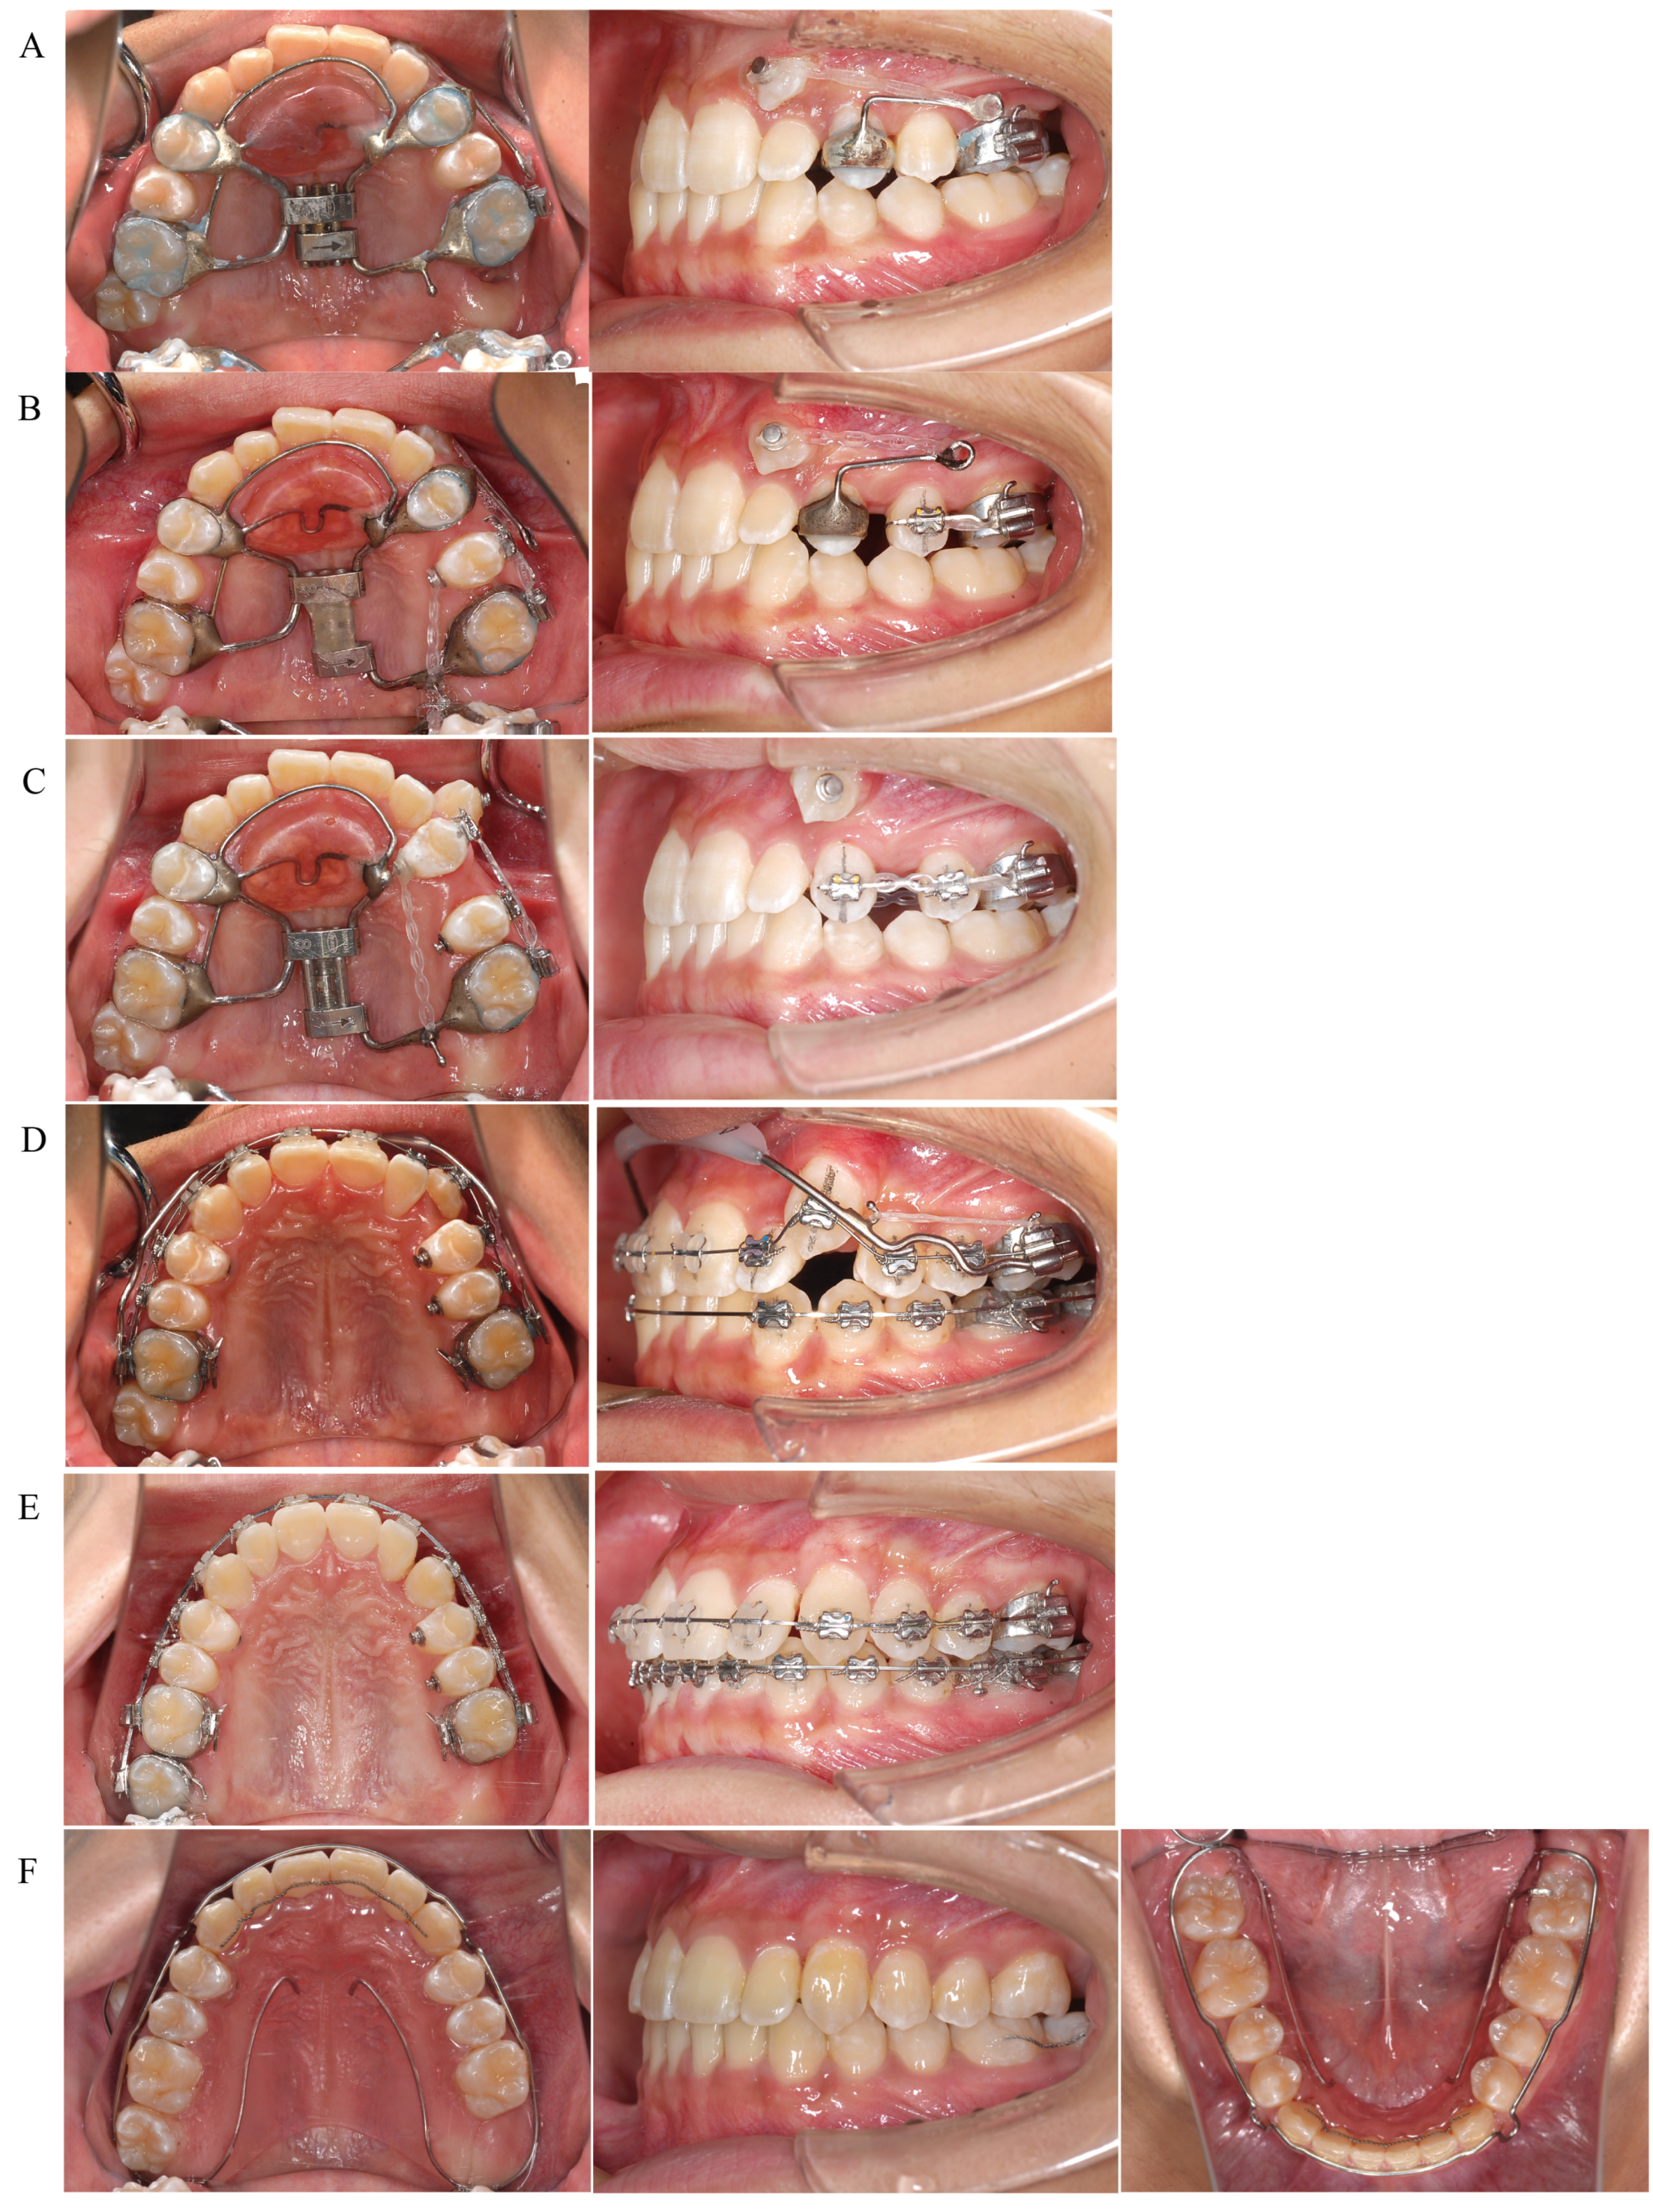

Figure 6. Treatment progress. (A) Orthodontic occlusal guidance appliance applied. Distal movement of the maxillary left first molar started. Traction of the maxillary left canine started. (B) Distal movement of the maxillary left first molar completed. A sectional archwire was placed on the maxillary left second premolar and first molar to start distal movement of the left second premolar. (C) Distal movement of the maxillary left second premolar completed. A sectional archwire was placed from the maxillary left first premolar to the first molar to start distal movement of the left first premolar. (D) Distal movement of the maxillary left first premolar completed. Leveling of the maxillary left canine started. A lip bumper was applied to the maxillary first molars reinforced anchorage. (E) Leveling completed. Detailing started. (F) Active treatment was terminated. Fixed retainers were placed between the maxillary and mandibular canines and on the mandibular left first and second molars. Maxillary and mandibular wraparound retainers were applied.

After extraction of the maxillary left second molar, a Hyrax-type expander was applied to the maxillary arch for distal movement of the maxillary left first molar. The patient was instructed to turn the screw a quarter-turn every 3 days. In parallel with the distal movement of the left first molar, traction of the left canine in the distal-buccal direction was initiated (Figure 6A). After about 3 months, when the patient had turned the screw a total of 32 times and an 8 mm expansion had been achieved, the occlusal relationship of the left molar was Angle Class I, indicating that the left first molar could be moved distally to the target position. The expansion screw was then fixed with resin to prevent relapse. A sectional archwire was placed on the left second premolar and first molar to initiate distal movement of the left second premolar (Figure 6B). Distal movement of the left second premolar was completed in 3 months. The left second premolar and first molar were sequentially ligated to prevent relapse of the second premolar. Then, the band on the left first premolar was removed, and a sectional wire was placed from the left first premolar to the first molar to initiate distal movement of the left first premolar (Figure 6C). After about 10 months, when the distal movement of the left first premolar was completed, the Hyrax-type expander was removed and an archwire was engaged in the left canine bracket to initiate leveling. In addition, to prevent the distally moved first molar from moving mesially, a lip bumper was applied to the first molars for reinforced anchorage during leveling (Figure 6D). After about 8 months, leveling of the canines was completed and detailing was initiated (Figure 6E). Three years and one month after the start of active treatment, detailing was completed and active treatment was terminated. Fixed retainers were placed between the maxillary and mandibular canines and on the mandibular left first and second molars, along with wraparound retainers, until the eruption of the maxillary left third molar. The maxillary wraparound retainer was designed to provide space for the eruption of the left third molar. The mandibular wraparound retainer was designed with a rest at the mandibular left second molar to prevent extrusion of the mandibular left second molar until the maxillary left third molar occluded with the opposing tooth (Figure 6F). Three years and six months after active treatment was terminated, the maxillary left third molar had fully erupted and occluded with the mandibular left second molar. We also encouraged the patient to have the mandibular left third molars extracted, because of no occlusal contact due to a reduced number of teeth in upper left segment. In addition, the maxillary and mandibular right third molars are impacted and scheduled for extraction.